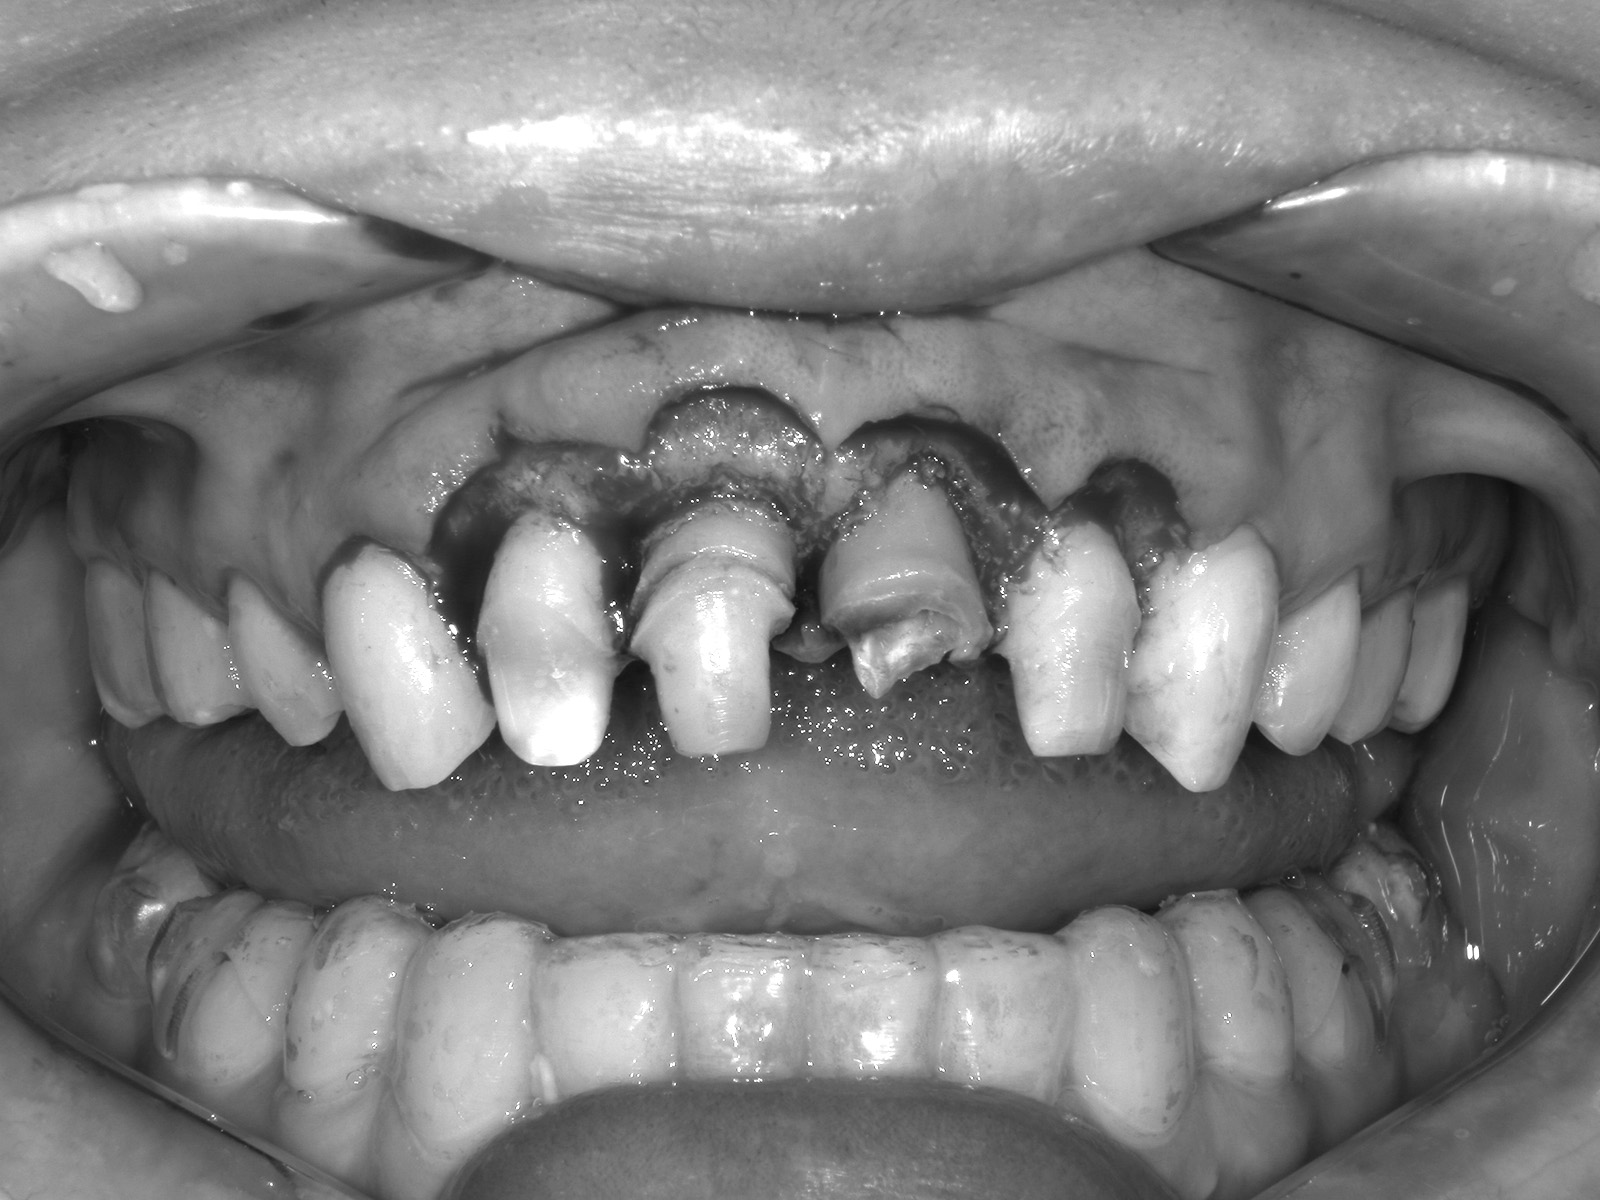

• 治療前

• 治療後

主訴右上の前歯が折れた 他院では抜歯と言われた

どのように治療したのかの具体的な説明そのままではかぶせ物がかぶせられないのでエクストルージョン(矯正による挺出)を行った後に、歯ぐきのラインをそろえるためのクラウンレングスニング(歯茎を切って開いて、歯を支えている骨を整える処置)したのちにジルコニアクラウンにて修復

治療期間途中精密仮歯による経過観察期間もあるので約半年

治療費36.3万円

その治療をすることで起こり得るリスク歯根(歯の土台部分)が短くなることによる、動揺や破折のリスクがあがる